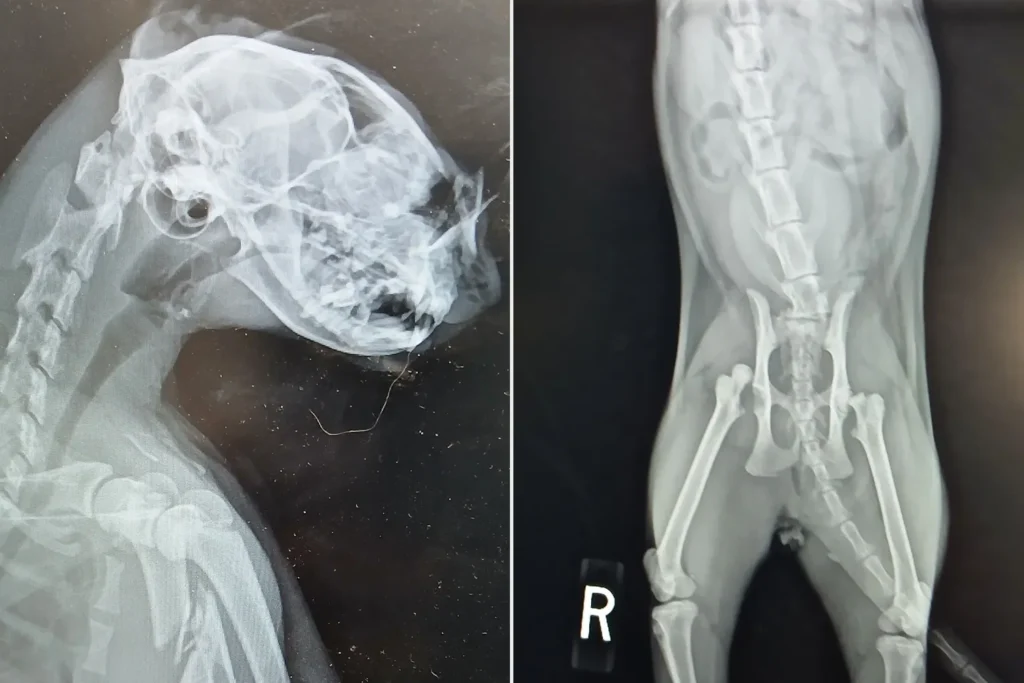

At South Shore Feral Care in West Babylon, staff assessed Garfield’s extensive damage: a complete fracture of his front limb, a broken nose, and two fractured hips.[1][2] X-rays revealed the severity of the limb break, yet the young cat remained alert and responsive. The facility assembled a veterinary team, including an orthopedic specialist, to manage pain and prepare for surgery.

Treatment costs have climbed toward $12,000, covering emergency procedures and postoperative care.[2] Despite the odds, caregivers emphasized his youth as a key advantage. “Despite everything he has endured, Garfield is alert, responsive, and fighting,” the group stated in an update. A second orthopedic evaluation will guide further steps.